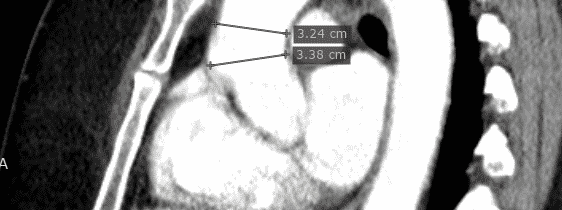

- Ich biete alle in der Praxis möglichen kardiologischen Untersuchungen und Möglichkeiten der Nachkontrolle inklusive implantierte elektronischer Geräte mit moderner Technologie an und arbeite mit allen kardiologischen Kliniken der Schweiz und dem Röngteninstitut IMAMED für weitergehende Untersuchungen zusammen. Ich investiere auch in technologische Fortschritte, die eine bessere oder weniger belastende Diagnostik erlauben. Aktuell habe ich das neueste Echokardiografiegerät von Philips als einer der Ersten in der Schweiz erworben (EPIC CVx). Ausserdem ist die Auswertung von Langzeit-EKG’s auf den neuesten Stand gebracht worden.